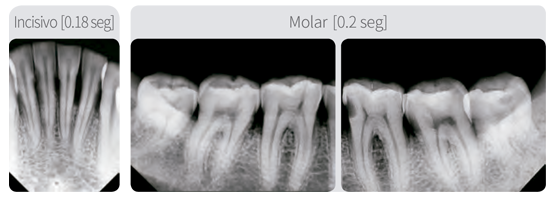

IMÁGENES MÁS CLARAS CON UN PUNTO FOCAL DE 0.4MM

A comparación de otros dispositivos en el mercado, EzRay Air W proporciona una calidad de imagen óptima y un valor agregado de diagnóstico adicional con su punto focal de 0.4 mm, independientemente del sensor intraoral que utilices.

* Condición de exposición 65kV, 3.0mA